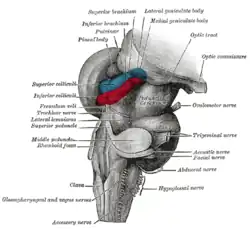

Die Zirbeldrüse liegt als unpaares Gebilde mitten (median) im Gehirn an der Hinterwand des III. Ventrikels über der Vierhügelplatte. Sie gehört zu den zirkumventrikulären Organen und wird anatomisch als Glandula pinealis sowohl zu den endokrinen Drüsen[2] gezählt, wie auch dem Epithalamus[3] zugeordnet.

Bei Fischen, Amphibien, Reptilien und vielen Vögeln ist die Zirbeldrüse als Scheitelauge noch selbst lichtempfindlich, bei Säugetieren gelangen von Lichtreizen ausgelöste Erregungen indirekt über Retina und Sehnerv zunächst in den Nucleus suprachiasmaticus im Hypothalamus. Der Nucleus suprachiasmaticus ist das primäre chronobiologische Zentrum der Säugetiere. Von hier ziehen Nervenfasern über die dorsale parvicellulare Unterabteilung des Nucleus paraventricularis, wo sie Synapsen mit absteigenden Bahnen zum Rückenmark aufnehmen. Diese absteigenden Bahnen ziehen zu den sympathischen Wurzelzellen (Nucleus intermediolateralis) im oberen Brustmark. Die Axone gelangen über den Halsteil des Sympathikus (bzw. Truncus vagosympathicus) wieder zurück kopfwärts zum Ganglion cervicale superius. Von hier wird die Information zur Epiphyse geleitet.[6]